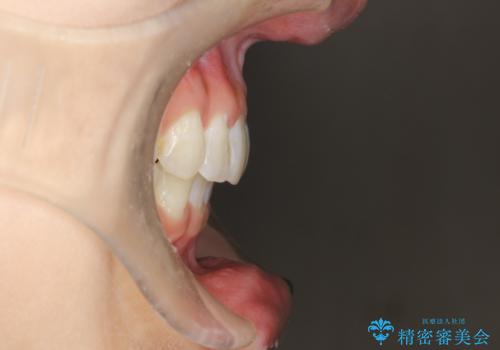

前歯のガタガタをインビザラインで矯正

- 前歯のがたつきを気にされて来院されました。

右上の前から2番目の歯が前方に大きく傾いており、下の前歯もガタガタしていました。

インビザラインにて、歯と歯のあいだをわずかに削り並べる計画としました。

しっかりとマウスピースを使用していただけたので、順調に治療を終えることができました